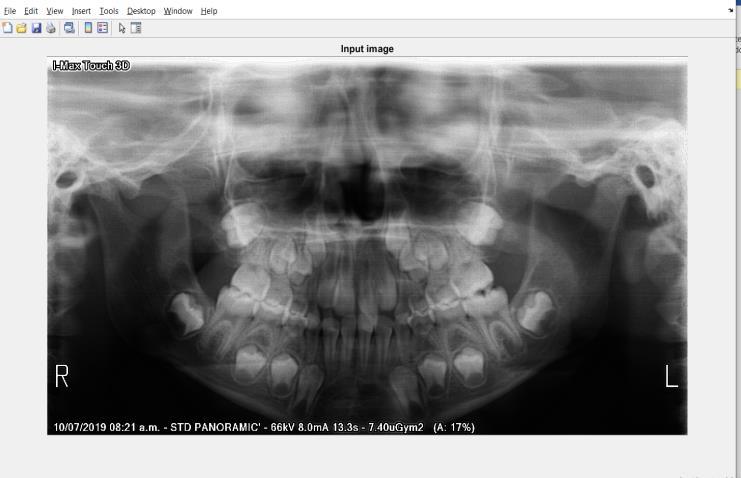

2.1. DATA COLLECTION

TheinputdatasetcomprisespanoramicX-ray(OPG)imagescollectedfromanopen-sourceKaggledataset.Additionally,raw imageswerecapturedusingaXiaomiRedmiNote9Pro64MPcameratoexpandthedataset.Theimagesrepresentpatients of various age groups and genders, with a focus on middle-aged individuals. Some images exhibit blue and grey tints, highlighting variations in imaging conditions. The dataset ensures diversity by including images of children, men and women,capturingarangeofdentalstructures.Thecollectedimagesserveasinputforthesegmentationmodels,providing real-worldvariabilityessentialforrobustmodelperformance.